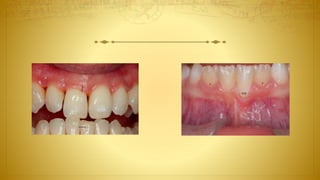

• Aberrant frenal insertions: Ankyloglossia? Blanching?

• Oral hygiene-induced or self-induced lesions

–– Stilman’s clefts? Incomplete (red) or complete (white) lesions

–– McCall’s festoons

–– Gingival erosion